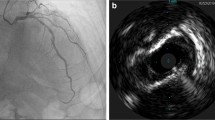

The American Heart Association [1] and European Society of Cardiology [14] in their consensus documents recommend using intravascular imaging only when coronary angiography is inconclusive for diagnosis of SCAD or to aid PCI when indicated for its treatment. Even though awareness about SCAD and its angiographic pattern recognition has improved among cardiologists in recent years, there are still cases when angiography alone may be inconclusive [19]. With greater use of intravascular imaging, SCAD is likely to be recognized as the underlying pathology for a larger subset of patients with MINOCA [13]. In such cases, intracoronary imaging is a valuable tool for diagnosis, since the pathology in SCAD involves the vessel wall rather than the lumen (Fig. 3). Intravascular imaging is particularly useful in type 3 SCAD which closely mimics atherosclerosis on a coronary angiogram. It is to be noted that intravascular imaging poses risk of propagation of coronary dissection due to guidewire entering the false lumen, hydraulic pressure from powerful contrast injections to opacify the vessel for some intravascular imaging modalities, or related to the guiding catheter itself (Fig. 4). Therefore, intracoronary imaging should be performed with great caution and should be reserved for cases where the diagnosis of SCAD is uncertain with routine angiography or to aid percutaneous coronary intervention (PCI) when deemed necessary [14]. Figure 6 shows a schematic representation of the role of intravascular imaging in SCAD and a comparison between the two modalities.

Intracoronary imaging of spontaneous coronary artery dissection by intravascular ultrasound (with outer border of false lumen arrowed, a) and optical coherence tomography showing partial (b) and circumferential (c) false lumens; the site of a fenestration (d) connecting true and false lumens and reduced light penetration through the false lumen (e). Three-dimensional image derived from segmentation of optical coherence tomography image showing how the false lumen tracks around the true lumen and is influenced (and frequently bounded) by side branches (f). Reprinted from Adlam et al. [14] with permission

Guidewire passage into the false lumen demonstrated by optical coherence tomography, with both wire (GW) and optical coherence tomography catheter (C) seen in the false lumen outside the compressed true lumen. Reprinted from Adlam et al. [14] with permission

IVUS has an axial resolution of 150 μm and is helpful in delineating intraluminal thrombus, intramural hematoma, intimal tear, and atherosclerotic plaque [14]. It has a greater depth of penetration compared to OCT, therefore allowing visualization of all the three layers of the vessel wall. IVUS is capable of delineating the true lumen from false lumen and is furthermore able to evaluate the extent of the false lumen and intramural hematoma (Fig. 5). The other benefit of this modality is that blood does not attenuate the ultrasound rays, and therefore, it obviates the need for pressurized contrast or saline injection, as is the case with OCT. Additionally, IVUS has a greater penetration depth (10 mm) allowing for visualization of the external elastic lamina and the entire dissected segment even in large caliber arteries or presence of intraluminal red thrombus [20]. The prime limitation of this technology is its relatively poor spatial resolution, as a result of which it is unreliable in identifying the site of communication between the true and false lumen (called the “entry point”) and the intima-medial layer. To mitigate this limitation, some experts recommend a combined use of IVUS and OCT for evaluation and management of SCAD lesions, although the costs of using two imaging modalities may be an impediment [21].

Intracoronary Images of SCAD from different patients using Optical coherence tomography (OCT) images. a Double lumen with a thick intimomedial membrane. b Double lumen with a thin intimal membrane. c Intimal rupture (arrow). d Intracoronary thrombus protruding into the true lumen (arrow). Intravascular ultrasound (IVUS) images. e Elliptical, echogenic, true lumen fully detached from the outer vessel wall. f Double lumen with a side branch (arrow) emerging from the true lumen. g Double lumen with false lumen thrombosis (plus sign). h Intramural hematoma. Notice the 3-layered appearance of the intimomedial membrane and the layered, crescent-shaped, intramural hematoma. Overall, the intimomedial thickness was better measured with OCT due to the better near-field resolution. However, this was challenging in 2 cases in which the dissection trailing edge progressively faded off into an underlying hematoma; IVUS, however, clearly displayed the true thickness of the flap. The true lumen tended to be smaller than the false lumen, and some segments showed an elliptical morphology suggestive of extrinsic compression. Asterisk denotes wire artifact. Reprinted from Paulo et al. [21] with permission

OCT allows visualization of the compromise in true lumen, size and extent of the false lumen, presence of associated thrombus, relationship of the false lumen to side branches, and presence of fenestrations, if any (Fig. 3). On OCT, the characteristic double lumen has been reported on all SCAD cases with either evidence of “entry tear” (connection between the true and false lumens) or intramural hematoma (Fig. 5). OCT also allows measurement of the thickness of the intimal-medial dissection membrane [22, 23]. Additionally, OCT also helps in identifying coronary vascular pathology associated with fibromuscular dysplasia (bright echogenic collagen bands interspersed with cellular hyperplasia), which co-exists and predisposes to SCAD. Follow-up OCT has also shed light on the stages of vessel healing with ultimate resolution of dissection or hematoma [25].